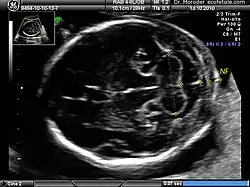

Measurements of fetal nuchal translucency, nasal bone and facial angle according to the standards of the Fetal Medicine Foundation

A nuchal scan or nuchal translucency (NT) scan/procedure is a sonographic prenatal screening scan (ultrasound) to detect chromosomal abnormalities in a fetus, though altered extracellular matrix composition and limited lymphatic drainage can also be detected.[1]

There are two distinct measurements: the size of the nuchal translucency and the thickness of the nuchal fold. Nuchal translucency size is typically assessed at the end of the first trimester, between 11 weeks 3 days and 13 weeks 6 days of pregnancy.[3] Nuchal fold thickness is measured towards the end of the second trimester. As nuchal translucency size increases, the chances of a chromosomal abnormality and mortality increase; 65% of the largest translucencies (>6.5mm) are due to chromosomal abnormality, while fatality is 19% at this size.[2] A nuchal scan may also help confirm both the accuracy of the pregnancy dates and the fetal viability.

Procedure

Nuchal scan (NT procedure) is performed between 11 and 14 weeks of gestation, because the accuracy is best in this period. The scan is obtained with the fetus in sagittal section and a neutral position of the fetal head (neither hyperflexed nor extended, either of which can influence the nuchal translucency thickness). The fetal image is enlarged to fill 75% of the screen, and the maximum thickness is measured, from leading edge to leading edge. It is important to distinguish the nuchal lucency from the underlying amniotic membrane.[9]

Normal thickness depends on the crown-rump length (CRL) of the fetus. Among those fetuses whose nuchal translucency exceeds the normal values, there is a relatively high risk of significant abnormality.